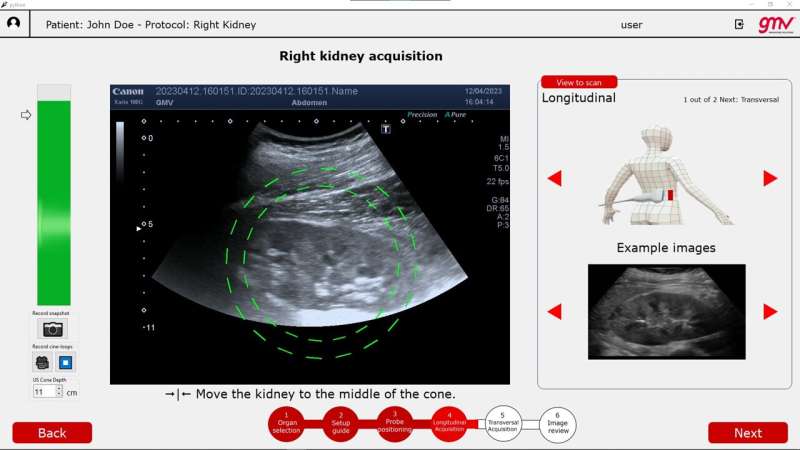

David Mirault of GMV says, "As we developed the system, ESA flight surgeons gave us essential feedback and guidance. Our aim was to make the user interface as intuitive as possible, so we had a group of entirely untrained physics students try out using it. Ultrasound images are noisy, blurry and contain plenty of artifacts such as shadows and speckle noise, and everyone's body is different. So medical professionals need years of specific courses and training to learn this diagnostic technique for a single organ. This means the chances of an untrained novice performing a successful ultrasound exam are essentially zero."

However ALISSE users receive detailed guidance of where in the body to place the ultrasound wand, are provided with example images of the target organ and given the percentage likelihood of the object in view being the correct target. The system is also able to differentiate between the clinically valuable long ways "plane detection mode" for an organ versus a less useful "transverse" side view.